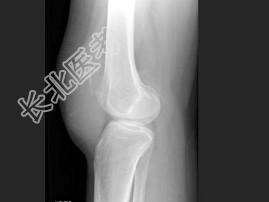

- 单项选择题女,30岁, 膝痛四月余,结合图像, 最可能的诊断是 ( )

A、畸形性骨炎

B、嗜酸肉芽肿

C、成软骨细胞瘤

D、骨囊肿

E、骨巨细胞瘤